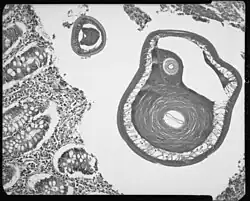

Mannetje en vrouwtje in slijmvlies -

Dwarsdoorsnede volwassen rondworm in wormvormig aanhangsel -

De eieren worden met de ontlasting doorgegeven.1. In de grond gaan de eieren over in een tweecellig stadium 2, vervolgens ontstaat na meerdere delingen een veelcellig stadium 3. Uiteindelijk komt de L1-larve in het ei uit 4; en worden de eieren in 15 tot 30 dagen besmettelijk. Na inname (door met grond verontreinigde handen of voedsel) komen de L-larven in de dunne darm uit de eieren. 5 Vervolgens vervellen de larven nog vier keer, waarna ze volwassen zijn en zich in de darm nestelen 6. De volwassen rondwormen leven in de blindedarm en aansluitende dikke darm en zitten met de voorste delen in het slijmvlies vastgeschroefd. De vrouwtjes beginnen 60 tot 70 dagen na infectie eieren te leggen. De vrouwelijke rondwormen in de blindedarm scheiden dagelijks tussen de 3.000 en 20.000 eieren uit. Ze kunnen ongeveer 1 jaar in leven blijven.